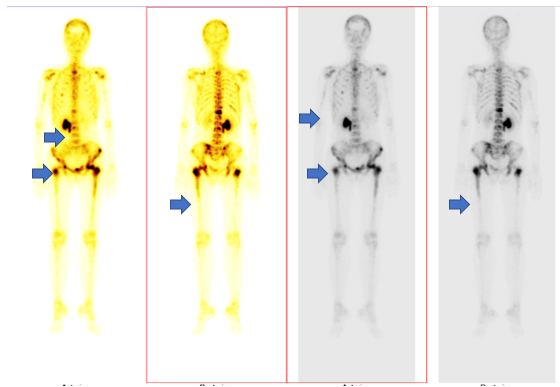

- Xạ hình xương: Hình ảnh tăng hoạt tính phóng xạ nhiều vị trí xương hộp sọ, nhiều đốt sống, xương cùng, xương cụt, nhiều xương sườn, xương cánh tay hai bên, xương chậu hai bên, xương đùi hai bên.

Hình 7

. Hình ảnh di căn xương đa ổ trên xạ hình xương (các mũi tên màu xanh)

- Xạ hình xương: Không phát hiện tổn thương xương nghi ngờ di căn

Hình 4

. Xạ hình xương chưa phát hiện bất thường